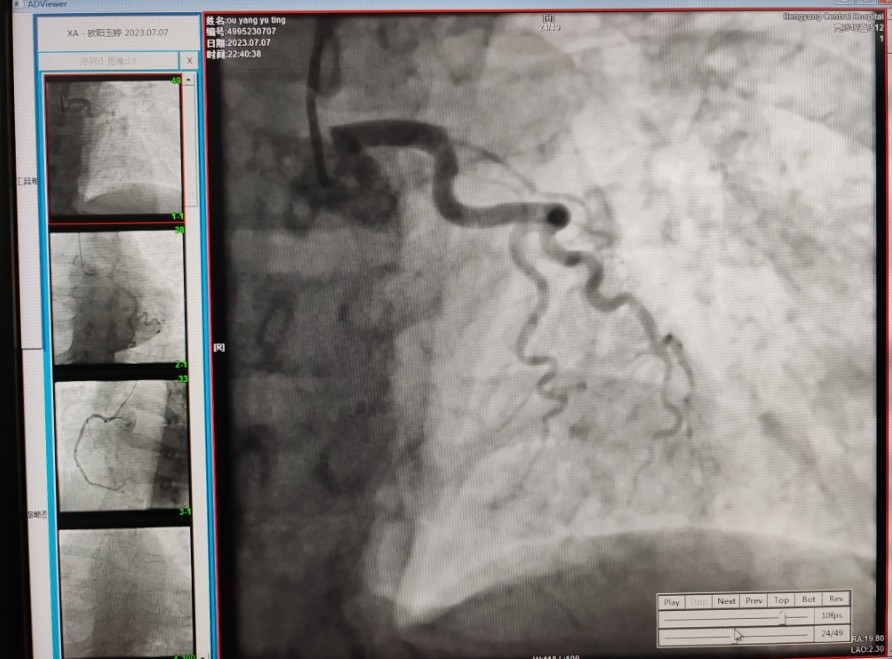

22:29分患者經(jīng)院內(nèi)綠色通道送達(dá)導(dǎo)管室,手術(shù)由雷剛副主任醫(yī)師主刀,楊繼賀副主任醫(yī)師為第一助手,介入技師及護(hù)士密切配合,聞訊而來的趙慶禧主任醫(yī)師坐鎮(zhèn)協(xié)調(diào)指揮。22:37分手術(shù)開始,冠脈造影顯示心臟上最重要的一條冠狀動脈-前降支開口齊頭閉塞,血管粗大且血栓高負(fù)荷,非??简?yàn)介入術(shù)者的手術(shù)能力,一旦發(fā)生冠脈無復(fù)流或操作不慎血栓帶入回旋支導(dǎo)致循環(huán)崩潰,病人幾乎無生還希望;此時(shí),患者手術(shù)臺上仍持續(xù)胸痛,且血氧飽和度在高流量吸氧狀態(tài)下不到80%,雷剛副主任醫(yī)師一方面指揮鎮(zhèn)靜鎮(zhèn)痛及抗心衰治療,一方面緊急啟用IABP(主動脈球囊反搏),然后精細(xì)操控細(xì)如發(fā)絲的介入導(dǎo)絲迅速通過病變,并予冠脈球囊擴(kuò)張、冠脈內(nèi)溶栓、抗痙攣藥物使用、植入冠脈支架,最終成功開通“罪犯”血管,且無手術(shù)并發(fā)癥發(fā)生,整個(gè)過程張弛有度、快慢結(jié)合、一氣呵成。患者術(shù)后胸痛明顯好轉(zhuǎn),血氧飽和度上升至96%,術(shù)后1天轉(zhuǎn)出監(jiān)護(hù)病房,第3天拔出IABP,目前已康復(fù)出院。